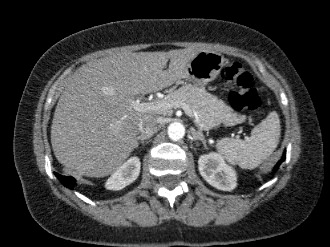

Мультиспиральная компьютерная томография (МСКТ) брюшной полости и забрюшинного пространства относится к современным лучевым методам исследования, с помощью которого можно оценить состояние органов брюшной полости (печени, желчного пузыря, поджелудочной железы, селезенки), забрюшинного пространства с расположенными в нем почками, надпочечниками, мочеточниками и прилегающих к ним кровеносных сосудов и лимфатических узлов.

С помощью мультиспиральной компьютерной томографии проводятся послойные рентгеновские снимки исследуемой области с толщиной среза от 0,5 мм. Затем полученные данные преобразуются в цифровые трехмерные модели органов и систем в мельчайших подробностях.

При подозрении на опухоли, воспалительные процессы, гнойные очаги назначается КТ брюшной полости и забрюшинного пространства с внутривенным болюсным контрастированием. Для этого пациенту внутривенно вводится рентгеноконтрастное вещество на основе йода. Благодаря усиленному кровоснабжению, которое обычно наблюдается в патологических очагах, препарат накапливается в структуре патологических образований и помогает врачу-рентгенологу выявить изменения внутренних органов.

Метод контрастирования помогает максимально точно выявить очаг патологии уже на начальной стадии, а также установить его локализацию, точные размеры, форму и особенности кровоснабжения. Возможности мультиспиральной компьютерной томографии позволяют выполнить своевременную диагностику заболеваний внутренних органов, от чего напрямую зависит эффективность лечения.